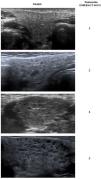

El resultado de la exploración oftalmológica y ecografía de glándulas salivales (EGS) se representa en la tabla 1. Los cambios observados en la EGS se representan en la figura 1.

Ecografías representativas de los cambios presentes en las glándulas salivales de los pacientes diagnosticados de síndrome de Sjögren juvenil. En todos los casos se representa la glándula submandibular, siendo las alteraciones bilaterales. La valoración de los cambios en una escala de 0 a 3 se realizó utilizando el SGUS (Salivary Gland Ultrasound Score), baremo de OMERACT (Outcome measures in Rheumatology) diseñado para cuantificar las alteraciones de la ecografía de glándulas salivales en pacientes con síndrome de Sjögren. Las variables analizadas incluyen la heterogeneidad del parénquima, la presencia de áreas anecoicas/hipoecoicas (micro- o macroquistes) así como la ecogenicidad del tejido que las rodea (normal o con fibrosis).